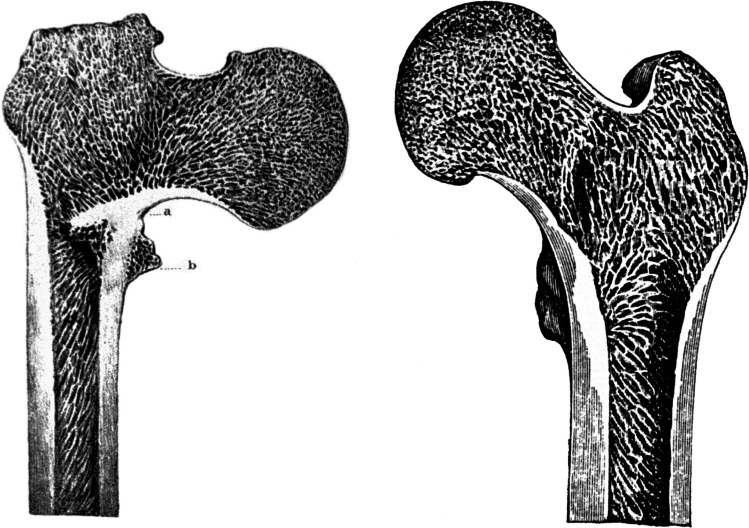

Fig. 1.

Original drawing of the Adams’ arch published by Smith in 1834

Fig. 2.

The first drawing of Adams’ arch in the German literature, published by Heppner in 1869

Fig. 3.

Drawing of the Adams’ arch published by Riedinger in 1874. a Anterior aspect; b coronal section